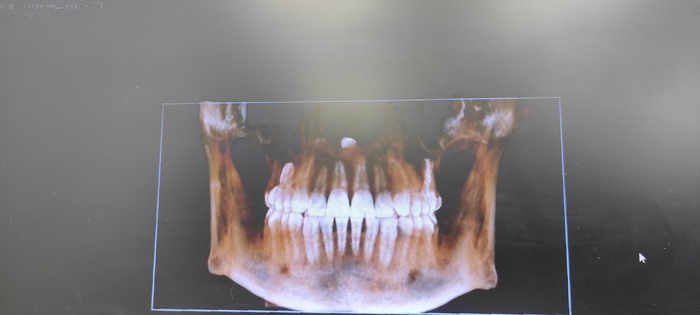

Кидаем снимки, если есть. Если есть КТ, то пишем "Есть КТ"